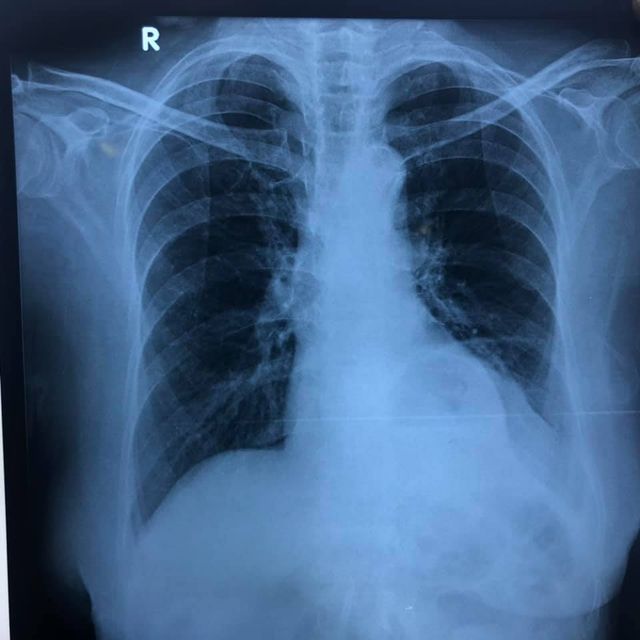

A beautiful case: Left sided Bochdalek Hernia

51 yr old patient with recurrent vomiting and dyspepsia and left sided chest pain. CT, Barium showed fundus and body of stomach in thoracic cavity with Mesentroaxial Volvulus. (image 1-4) Pre-OP thought to be a large sliding paraesophageal hernia operative findings revealed a posterior defect separate from hiatus suggestive of Bochdalek diaphragmatic hernia with a small hiatal hernia. Repair of Bochdalek defect with Crural repair was performed with mesh reinforcement. A 270 degree fundoplication was added (instead of a 360 as Manometry could not be performed preoperatively) (image 6-10) postoperative recovery was smooth (preop-postop xrays image 11-12).